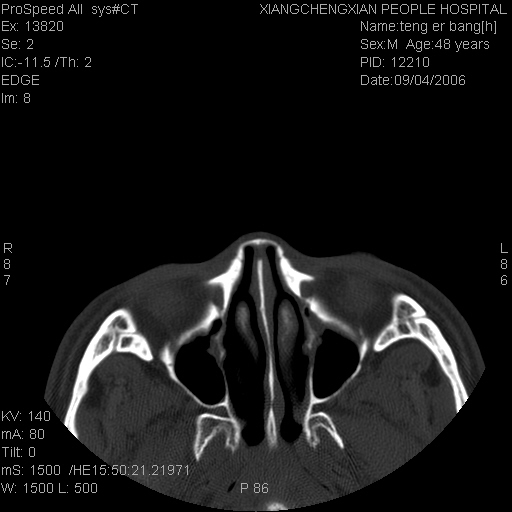

患者,男,以头面部外伤后头疼1小时为主诉入院,患者1小时前被他人打伤头部及左侧面部,眼睑无水肿,左侧面部肿胀压疼,未触及骨擦音。专科检查:耳鼻喉未见异常。

ct:平扫+冠扫:双侧鼻骨对比,冠扫s6#示右侧鼻骨尖部可见线状低密度影,边缘光滑,并见硬化.软组织未见肿胀.

诊断意见:鼻额缝(鼻骨与上颌骨额突缝),但个别同志认为是骨折.因此请同行们会诊.多谢了!

正常鼻颌缝。软组织无肿胀。鼻腔无积液积血。鼻骨光滑规整无中断。均不支持骨折。

正常的,双侧对称.边缘光整,且逢等宽.

正常鼻颌缝。软组织无肿胀。鼻腔无积液积血。鼻骨光滑规整双侧对称。均不支持骨折。